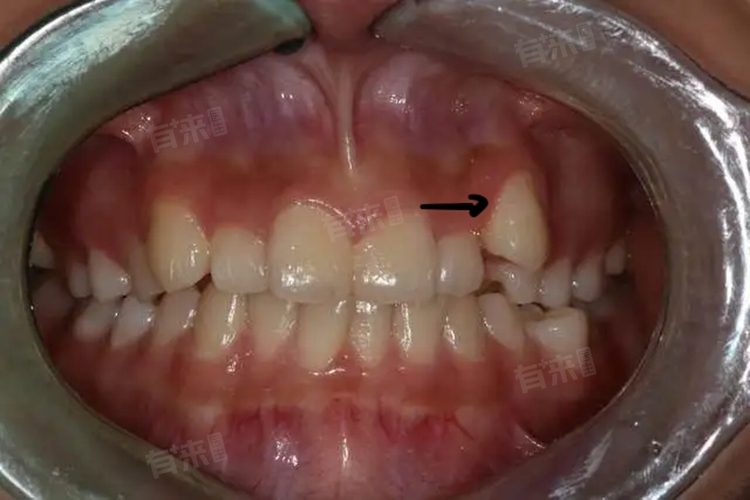

2、上颌尖牙生长较晚:上颌尖牙,即我们通常所说的虎牙,是口腔中从中间数第三颗牙齿。这颗牙齿往往生长得比其他牙齿晚,通常在其他牙齿已经长好后才开始生长。由于其生长时间较晚,且位置相对有限,当上颌尖牙在牙列、牙弓中没有足够的空间生长时,就可能向外突出,形成虎牙。

4、局部间隙不足:除了上述原因外,局部间隙不足也是导致虎牙形成的重要因素。在牙齿排列过程中,如果口腔内的间隙不足以容纳所有牙齿的正常生长,那么某些牙齿就可能因为受到挤压而向外突出。对于上颌尖牙来说,由于其生长位置相对特殊且容易受到周围牙齿的影响,因此在间隙不足的情况下更容易形成虎牙。